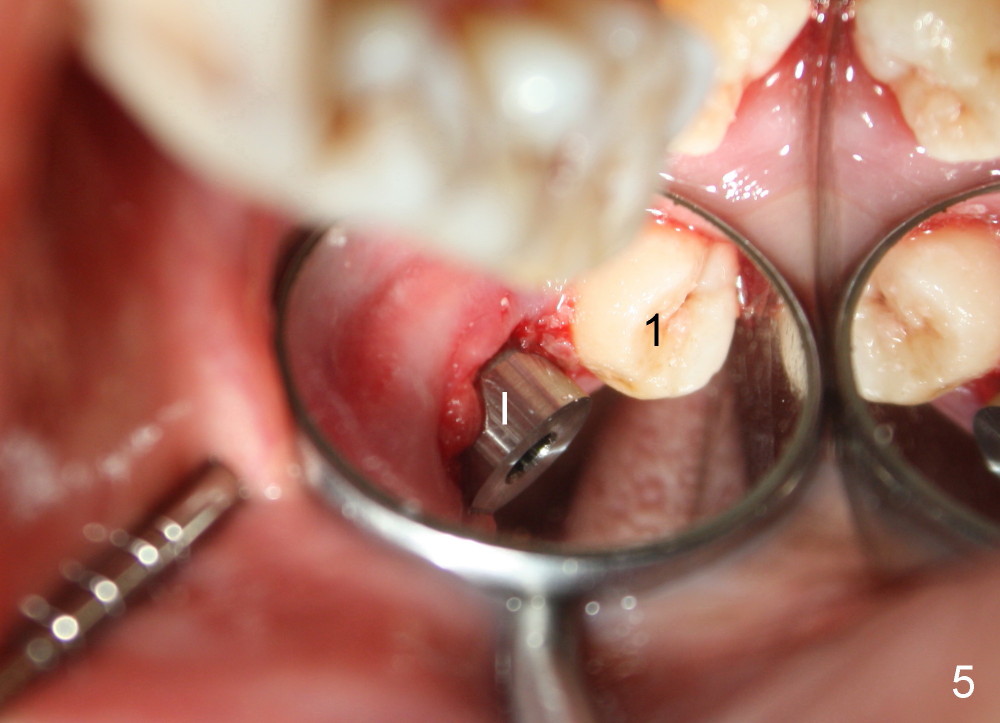

A 48-year-old lady is a dental phobic and has generalized chronic periodontitis. Bone loss around the tooth #2 has been severe for the last 5 years (Fig.1,2 *). Finally she agrees to have #2 (symptomatic) extracted and immediate implant placed (Fig.3 I). A 7x17 mm implant has to be used to achieve primary stability. The remaining buccal and lingual gaps are filled with allograft and membrane (Fig.4 *). Fig.5 shows that there is a space between the tooth #1 (asymptomatic) and the immediate implant (I). The wound/socket is protected by applying perio dressing around an abutment (Fig.6 A). Postop the patient is pain free; the perio dressing dislodges by itself. She returns 3.5 months later for restoration; but the tooth #1 has shifted mesially (Fig.6 arrow). The patient is not so willing to have #1 removed. Bands and bracket are placed in the neighboring teeth including a provisional crown to move the shifted tooth (with mobility) distally (Fig.7,9). The 2nd reason for #1 shifting is abnormal occlsual scheme on the right posterior region (Fig.8); mobility of #1 is the 1st one. The 3rd one is probably bruxism. In 5-6 weeks, the tooth #1 has moved to a desirable position (Fig.10, as compared to Fig.3,5). There is enough space for restoration (Fig.11,12).